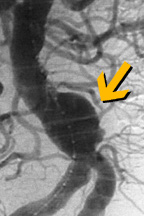

حديثا بدأ الأخصائيون بإستعمال تقنية غير جراحية لمعالجة المرضى ذوي الحالات الخطرة جداً لتمدد الأوعية الدموية الأبهري البطني. هذه التقنية مفيدة للمرضى الذين لا يمكن لم الخضوع للجراحة بسبب وضعه الصحي.

الإجراء يتضمن إستعمال قسطرة لإدخال أداة تسمى وصلة حلقة فاتحة Stent Graft. الحلقة الفاتحة توضع داخل الشريان في موقع التمدد. يجرى الدم خلال الحلقة الفاتحة، مما يؤدي إلى خفض الضغط على جدار الشريان الضعيف. هذا الإنخفاض في الضغط يمكنه أن يمنع التمدد من تفجير الشريان.